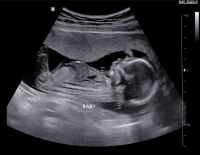

• Siêu âm

Dịch Vụ Siêu Âm